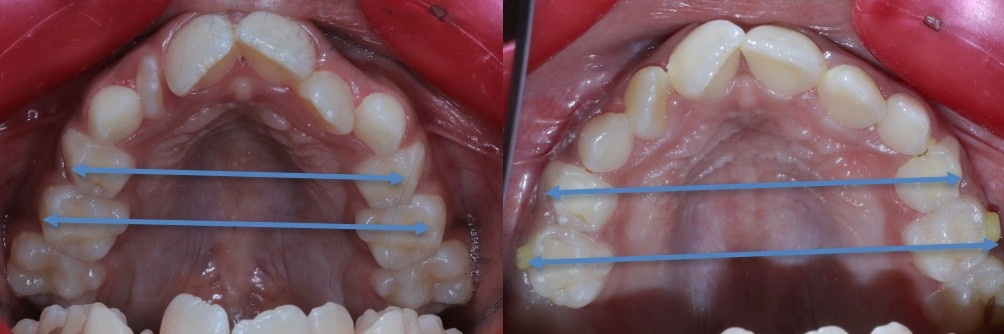

Before & After Expansion

If you want to understand the complete palatal expander before and after timeline, including changes in smile width, breathing and jaw development, check our detailed guide here.